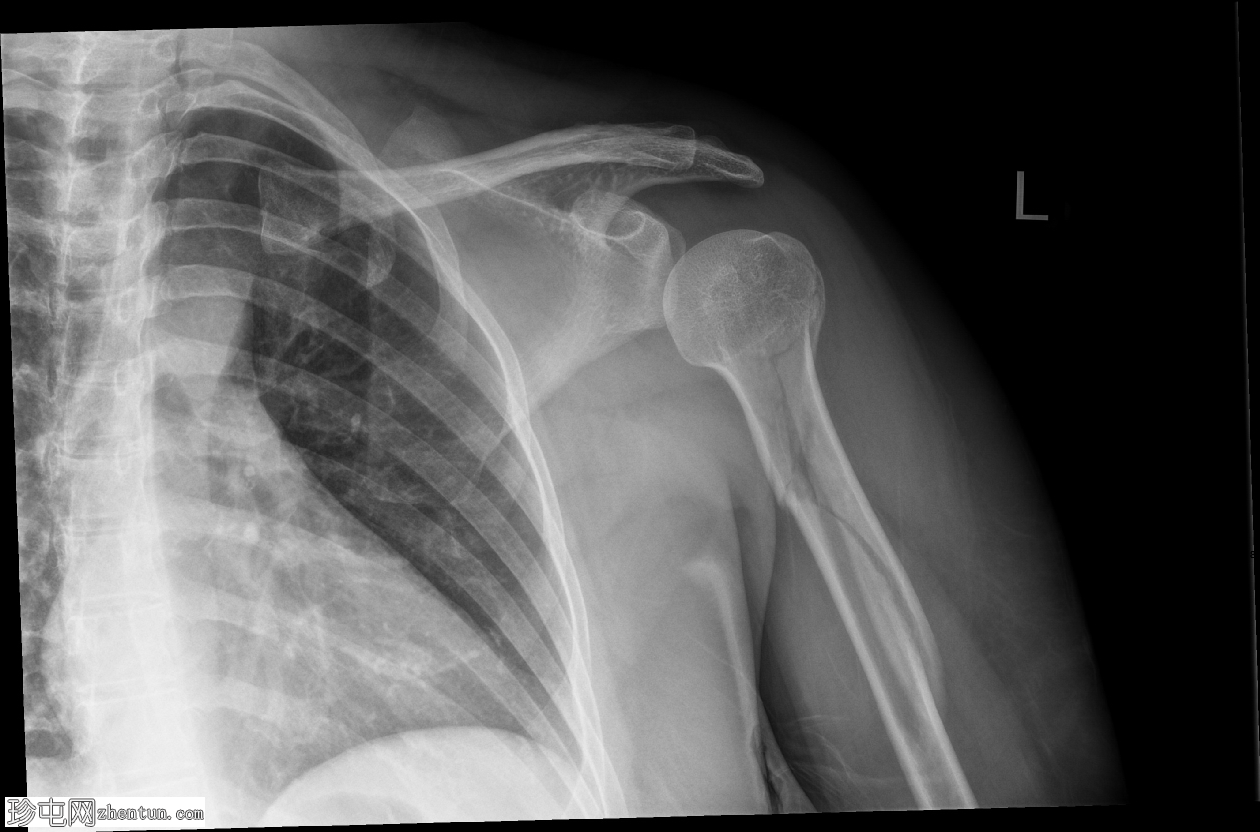

斜位

肱骨近端粉碎性移位骨折,累及骨干近端半部、外科颈,并延伸至大结节。

肱骨头在肩关节内向下半脱位,肩峰肱骨间距增大。